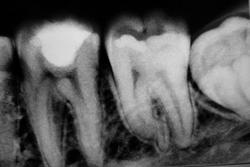

к стоматологу терапевту. об удалении и речи быть не может. грануляционные изменения вокруг корней 6 и 7 зуба. хроническое воспаление и больше ничего.

A кроме периодонтита больше ничего нет? Корешочек не сломан?

Оба зуба-удалять, разрушена бифуркация.